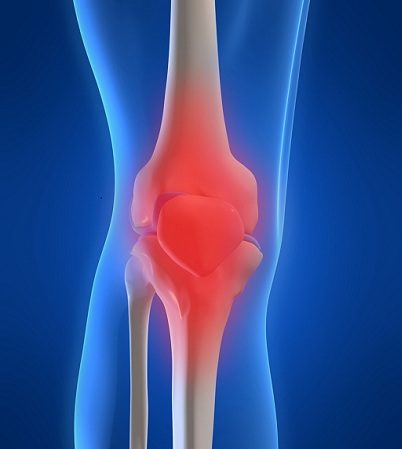

ΠΑΝΗΓΥΡΑΚΗΣ ΝΕΚΤΑΡΙΟΣ

ΟΡΘΟΠΑΙΔΙΚΟΣ ΧΕΙΡΟΥΡΓΟΣ

- Αρθροσκοπική χειρουργική

- Ολική αρθροπλαστική γόνατος ισχίου